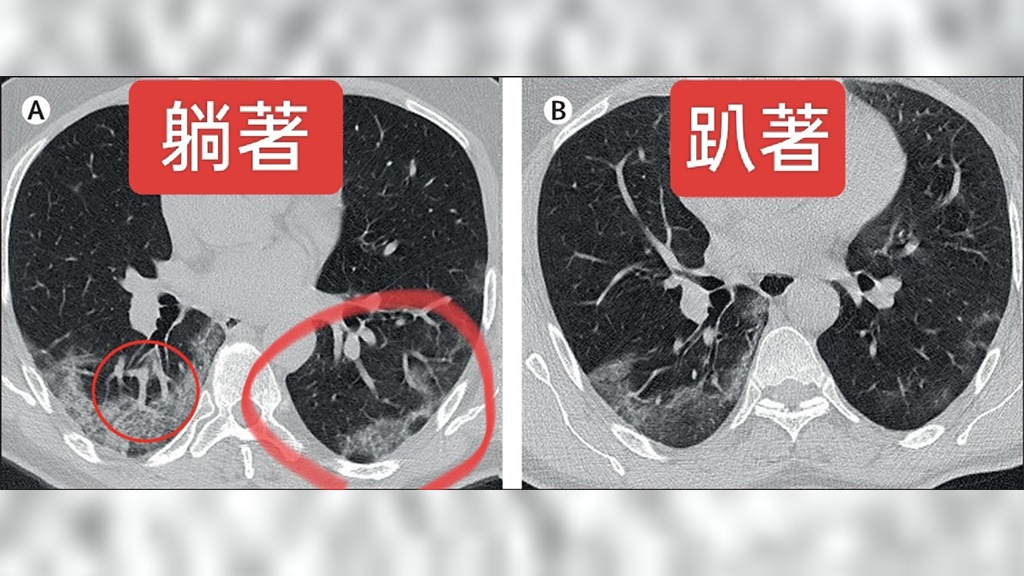

蘇一峰說明,依照解剖位置,心臟就在肺部的左前方,當人躺下時,心臟就會壓在肺臟的上方。所以每一次呼吸,肺臟都要支撐起心臟的重量。他引用來自知名醫學期刊《刺胳針(Lancet)》的圖片來說明。

圖片是以一位COVID肺炎患者在同一時間分別進行仰臥和俯臥的電腦斷層掃描,從圖中可以清楚看到,仰臥時因為心臟的壓迫,肺炎的情況明顯更加嚴重;而俯臥時在沒有心臟壓迫的情況下,兩側肺炎的情形都有所改善,一側的肺炎甚至完全消失了。